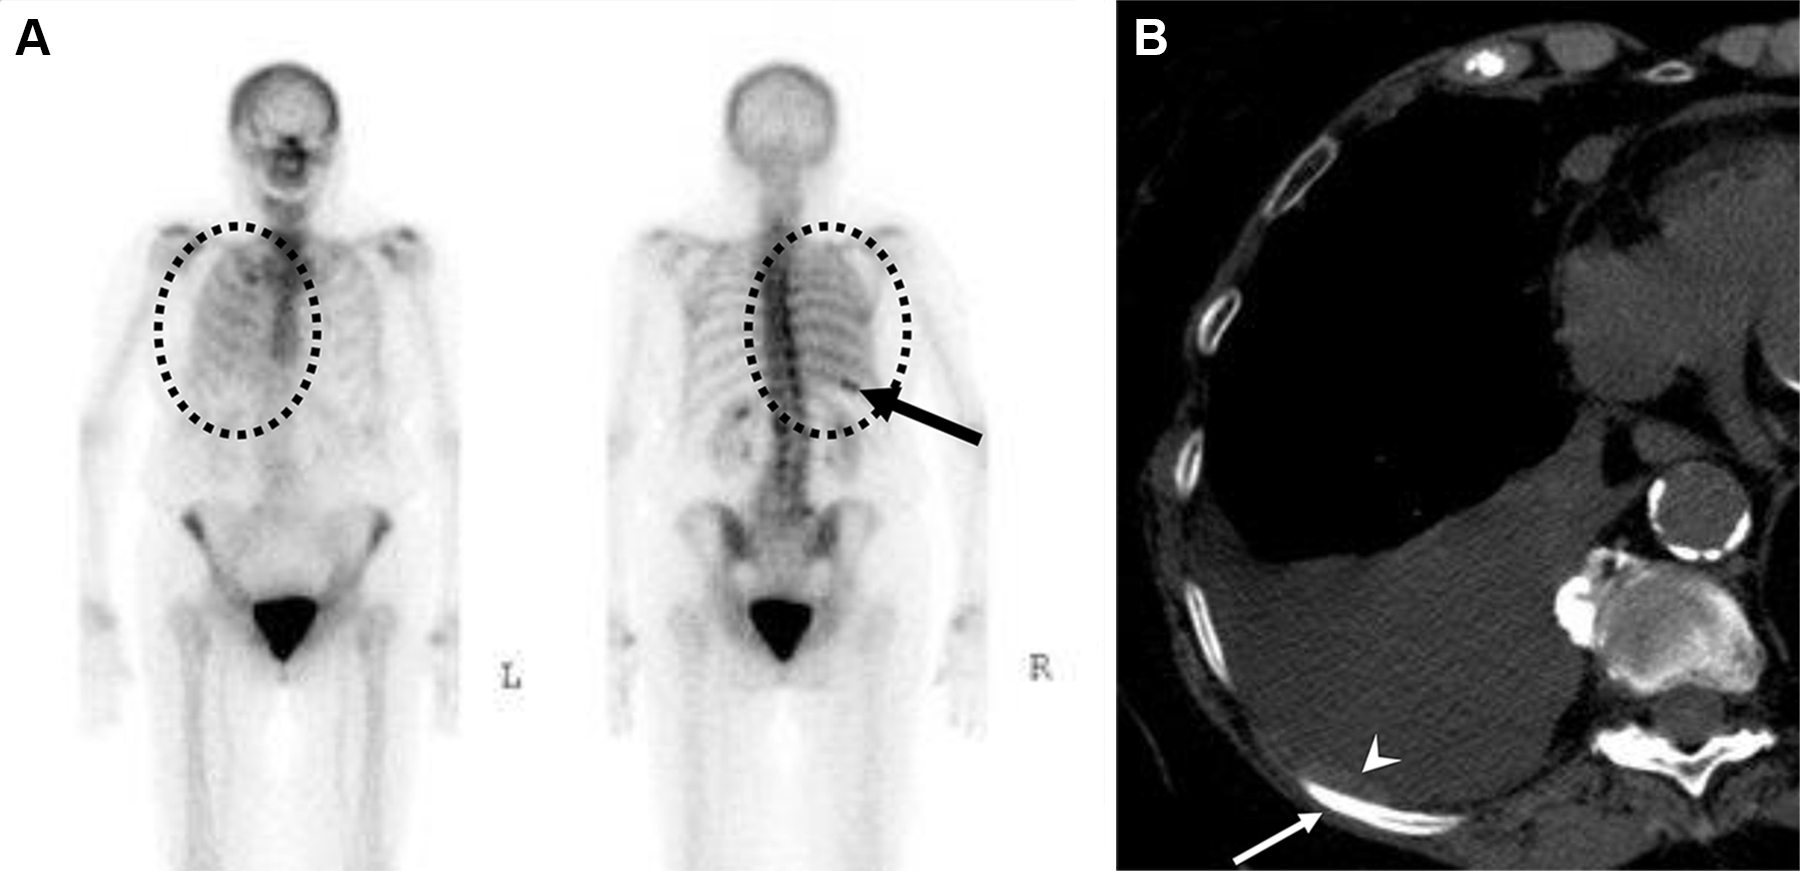

Metastasi costali e pleuriche con versamento pleurico in una donna di 63 anni con tumore al seno.

La scintigrafia ossea con 99mTc-MDP evidenzia una lieve ipercaptazione diffusa che ricalca l’emitorace destro, causata verosimilmente dall’accumulo di tracciante nel liquido pleurico maligno. È inoltre visibile una captazione longitudinale a carico dell’arco posteriore dell’XI costa destra. La TC conferma la natura della captazione, evidenziando il versamento pleurico, un ispessimento pleurico e le iniziali alterazioni osteosclerotiche a carico della costa interessata. Il caso dimostra come la scintigrafia ossea possa rilevare non solo le localizzazioni secondarie scheletriche dirette, ma anche segni indiretti di patologia extra-ossea adiacente (come la captazione pleurica).